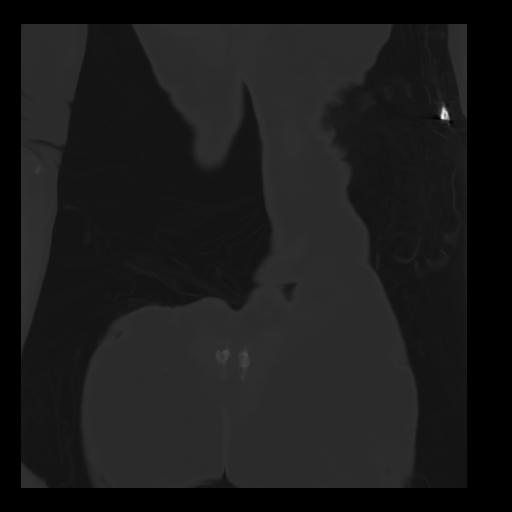

35 CUERPO,CE,Coronal,3.000,CUERPO,Coronal,